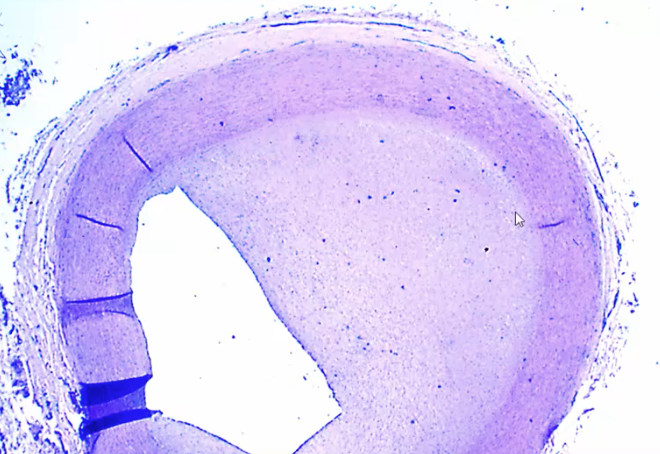

Intima is markedly markedly thick, this is Takayasu arteritis

Tunica media is completely normal whereas the intima is markedly thick, this is takayasu arteritis

Granulomatous inflammation seen in the aorta as part of the Takayasu arteritis